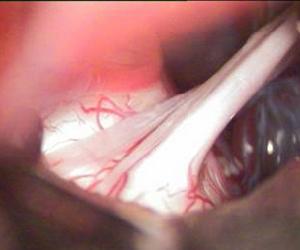

1. 眼神經(n.ophthalmicus)在三支中最小,只含有一般軀體感覺纖維,眼神經向前進入海綿竇外側壁,經眶上裂入眶,分布於額頂部、上瞼和鼻背皮膚,以及眼球、淚腺、結膜和部分鼻腔黏膜)。

(1) 淚腺神經 細小,沿眶外側壁、外直肌上緣前行至淚腺分布於淚腺和上瞼的皮膚。

(2) 額神經 較粗大,位於上瞼提肌的上方,分2~3支,其中眶上神經較大,經眶上切跡,分支分布於額頂部皮膚。

(3) 鼻睫神經 在上直肌的深面,越過視神經上方達眶內側壁。此神經分出許多分支,分別分布於眼球、蝶竇、篩竇、下瞼、淚囊、鼻腔黏膜和鼻背皮膚。2. 上頜神經(n.maxillaris) 也是一般軀體感覺神經,自三叉神經節發出後,立即進入海綿竇外側壁,之後經圓孔出顱,進入翼齶窩,再經眶下裂入眶,續為眶下神經。上頜神經分支分布於上頜各牙、牙齦、上頜竇、鼻腔和口腔的黏膜以及瞼裂間的面部皮膚